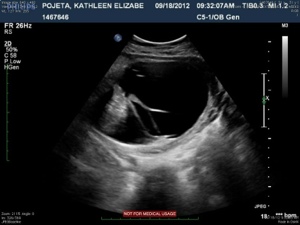

This image shows the bottom portion of the spine (lumbar and sacral). The large black area surrounded by a jelly-bean type shaped white line is the cyst, or sac.

The next four images just show various views of the strands/septations that are visible within the sac.